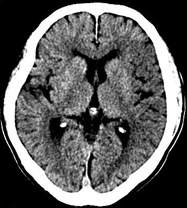

如上圖所示,相鄰的三張軸位圖像未見明顯異常,根據(jù)傳統(tǒng)軸位圖像很難得到準確的臨床診斷。

同一病人利用容積數(shù)據(jù)進行三維處理后,高品質(zhì)MPR和三維圖像上則清晰顯示了縱向排列的腹腔干與腸系膜上動脈相鄰近,血管發(fā)生變 異,近端血管閉塞,為臨床提供了精確的診斷信息。